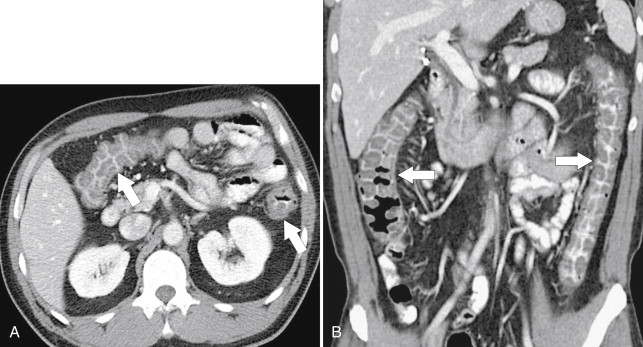

Often the infectious etiology cannot be determined by imaging alone because all the agents cause nonspecific colonic wall thickening and some cause a pancolitis, including Escherichia coli (although this colitis can be severe [ Fig. 5-47 ]) and those involved in traveler’s diarrhea ( Fig. 5-48 ). Other pathogens tend to affect specific colonic areas more than others. Campylobacter sp. is sometimes indistinguishable from UC ( Fig. 5-49 ), but is often confined to the rectum. Other rectal colitides include gonococcal and herpes colitis. Shigella sp. primarily affects the left side of the colon, whereas Salmonella typhi, tuberculosis, Yersinia, and amebiasis are focally confined to the ileocecal region with or without local adenopathy.

Figure 5-47, Axial ( A ) and coronal ( B ) contrast-enhanced CT in a 12-year-old boy with marked colonic thickening ( arrows ), particularly the right colon due to E. coli colitis.

Figure 5-48, Axial ( A ) and coronal ( B ) contrast-enhanced CT in a 64-year-old woman with pancolitic mucosal thickening ( arrows ) due to traveler’s diarrhea.